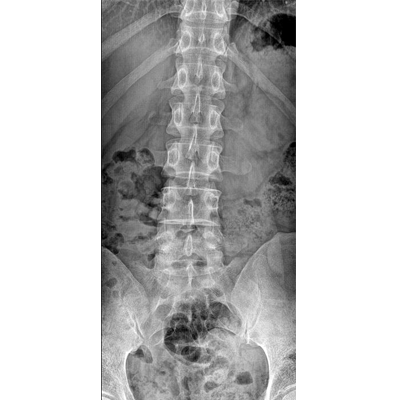

●大尺寸非晶硅平板探測器。

●非晶硅平板探測器,采用先進的制造工藝、性能更穩定。

●探測器可以大范圍轉動,大尺寸有效探測面積,可滿足人體多部位攝影需求。